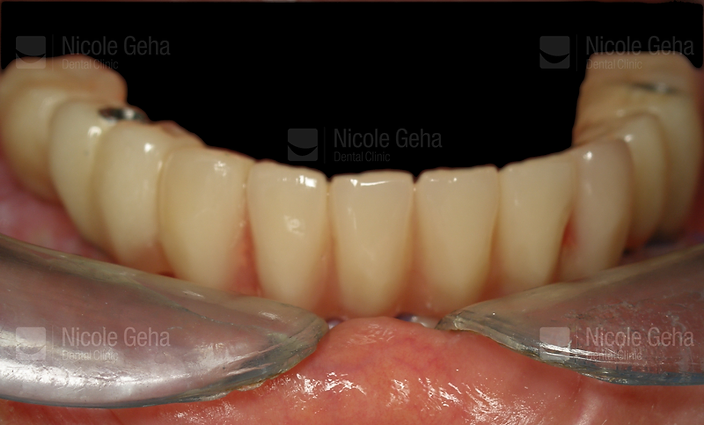

Final restoration after 4 months